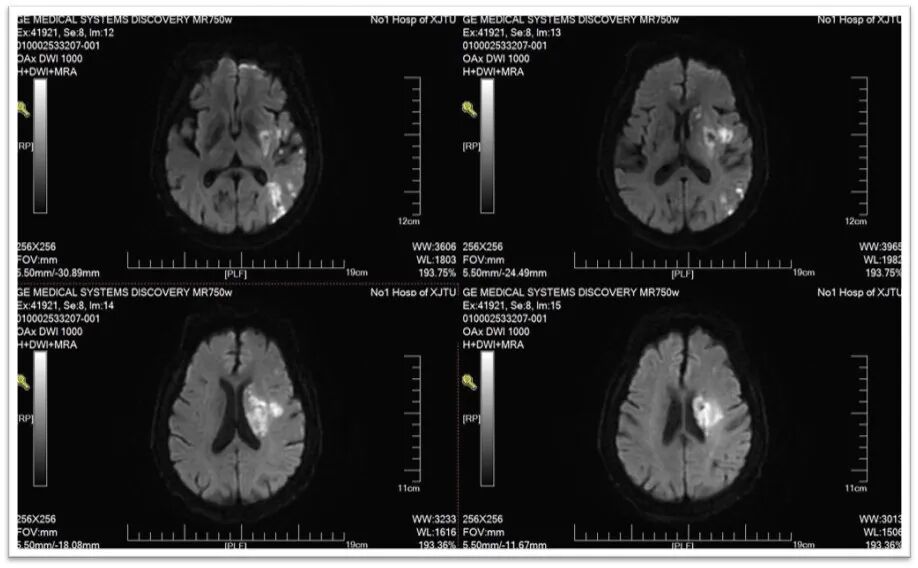

图2:头颅DWI提示左侧侧脑室旁基底节区新鲜脑梗死;